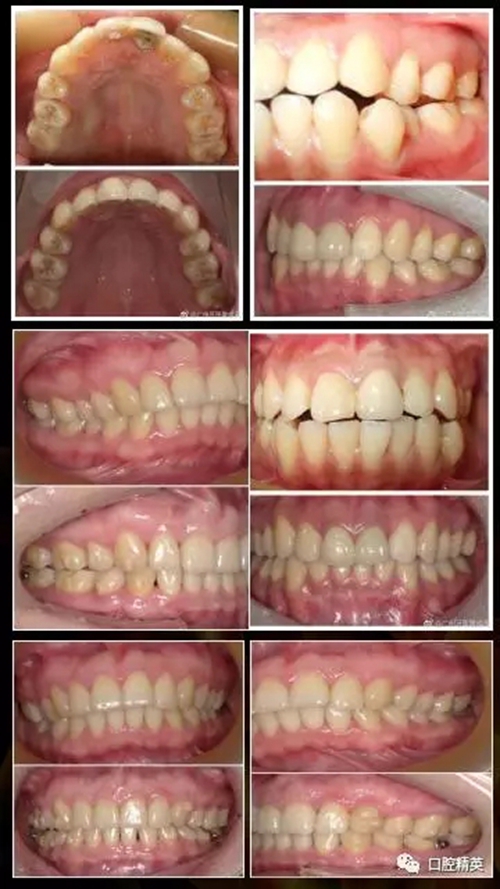

樊老師近期隱形矯正病例: